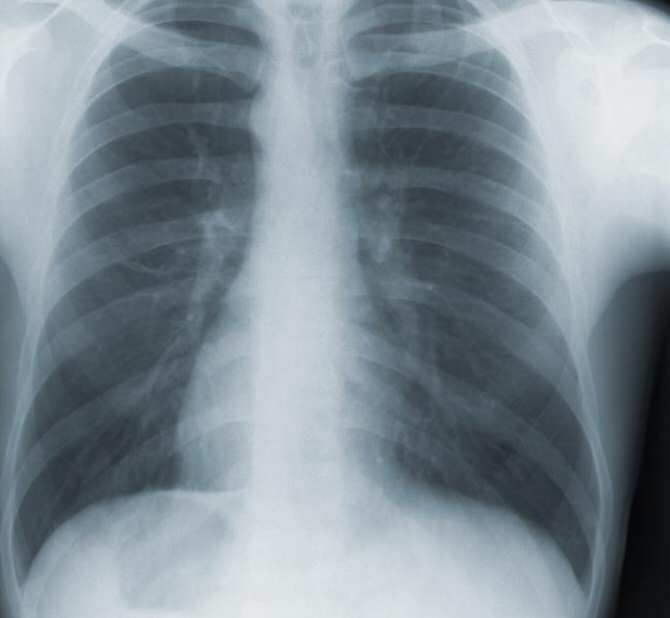

Aunque útiles, bastantes de las técnicas de diagnóstico médico tradicionales resultan muy aparatosas. En la imagen, parte de una radiografía de tórax. (Foto: CDC / Phyllis Q. Edwards)